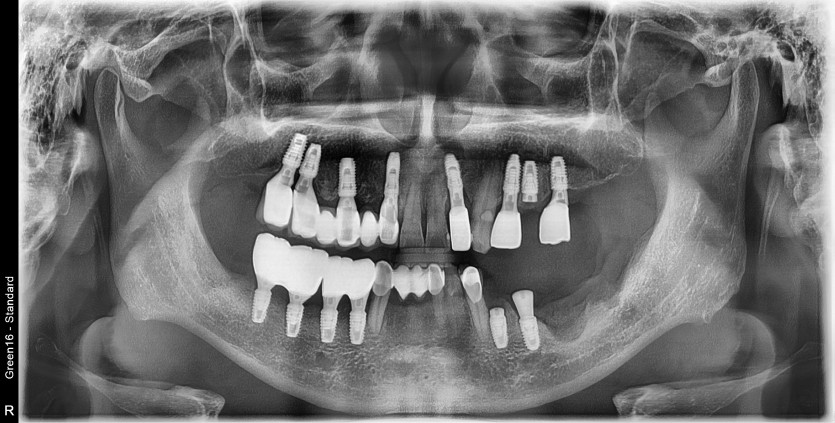

30번대 임플란트 재수술